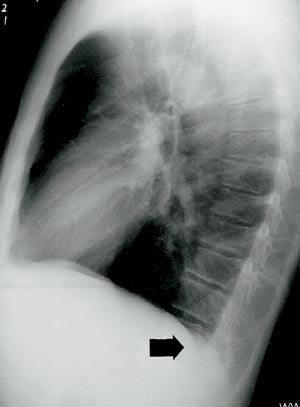

Røntgen thorax viste intet sikkert patologisk. CT thorax viste imidlertid svarende til høyre underlapp forstørrede karstrukturer med kraftige tilførende og fraførende kar, forenlig med en stor arteriovenøs fistel med kraftig shunting (fig 2).

Vi oppfattet dette som den mest sannsynlige årsak til pasientens lillehjerneslag. Grunnet den uttalte blødningstendensen ble han ikke gitt antitrombotisk behandling. Han ble henvist til thoraxkirurgisk avdeling, der han seks uker senere ble vellykket behandlet med endovaskulær okklusjon (embolisering) av fistelen.

Sykehistorien viser at røntgenbilder av lungene er viktig i rutineutredning ved hjerneslag. Hos vår pasient ble røntgen thorax først oppfattet som normalt, men etter at CT thorax hadde påvist en fistel, kunne denne også ses på standard røntgen thorax ved grundig gransking av bildene (fig 3).